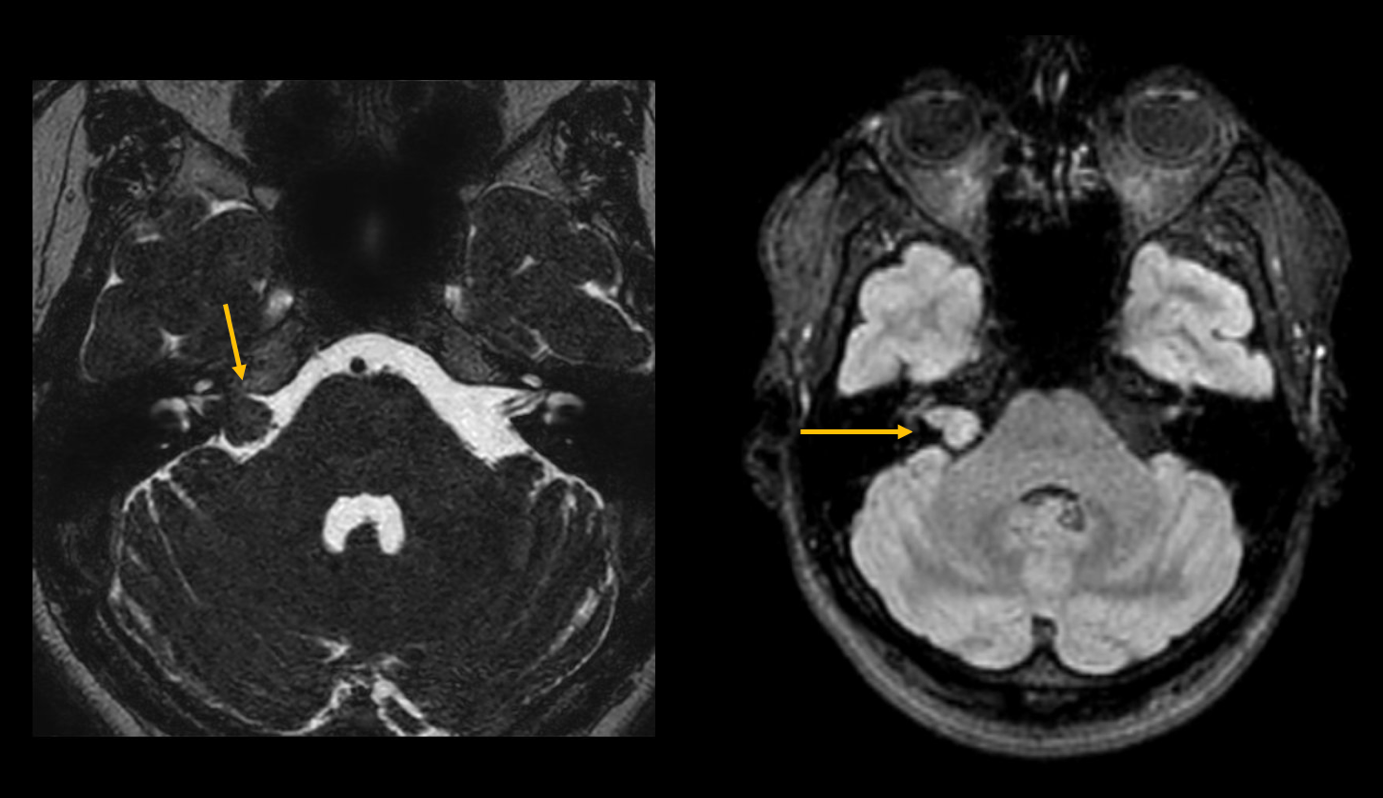

L'acufene non è inizialmente una malattia a sé stante, ma un sintomo di vari disturbi. All'inizio, spesso sono presenti danni e malattie nell'orecchio stesso, ad esempio a causa di un'infiammazione o di una forte esposizione al rumore. Se i sintomi peggiorano, è consigliabile sottoporsi a una risonanza magnetica (RM). A una paziente di 47 anni (vedi foto) è stato diagnosticato un neurinoma acustico sul lato destro, con conseguente perdita dell'udito.

Figura 2: RM della fossa posteriore con ponderazione T2 e T1. Mostra una massa isointensa in T2-W nel meato acustico interno, coerente con un neurinoma acustico.